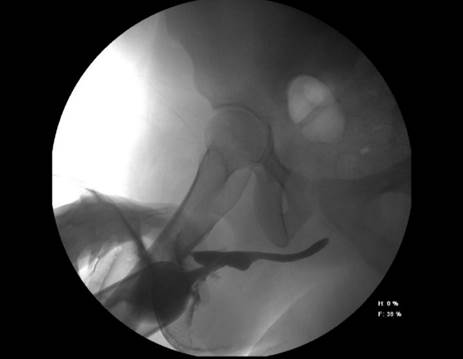

Paciente masculino de 21 años, con antecedente de hipospadias de uretra peneana distal, precedente de siete intervenciones quirúrgicas previas para corrección de hipospadias fallidas durante la niñez y adolescencia, acude a consulta por presentar micción a diferentes niveles de la uretra peneana distal (Figura 1), uretrocistografía del hipospadias (Figura 2) y solicita tratamiento para resolverlo.

Figura 2 Se observa fuga de medio de contraste a nivel central y permeabilidad de uretra distal y proximal a jeringa con medio de contraste